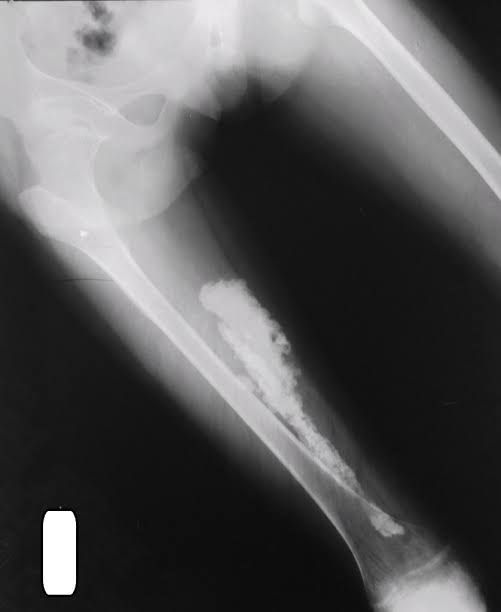

Myositis ossificans

Myositis ossificans (my-uh-SY-tuss uh-SIH-fuh-kanz) is when a bone forms inside your muscle or other soft tissue. Usually, myositis ossificans develops after a traumatic injury. Most often, it affects large muscles, such as in your arms or legs.